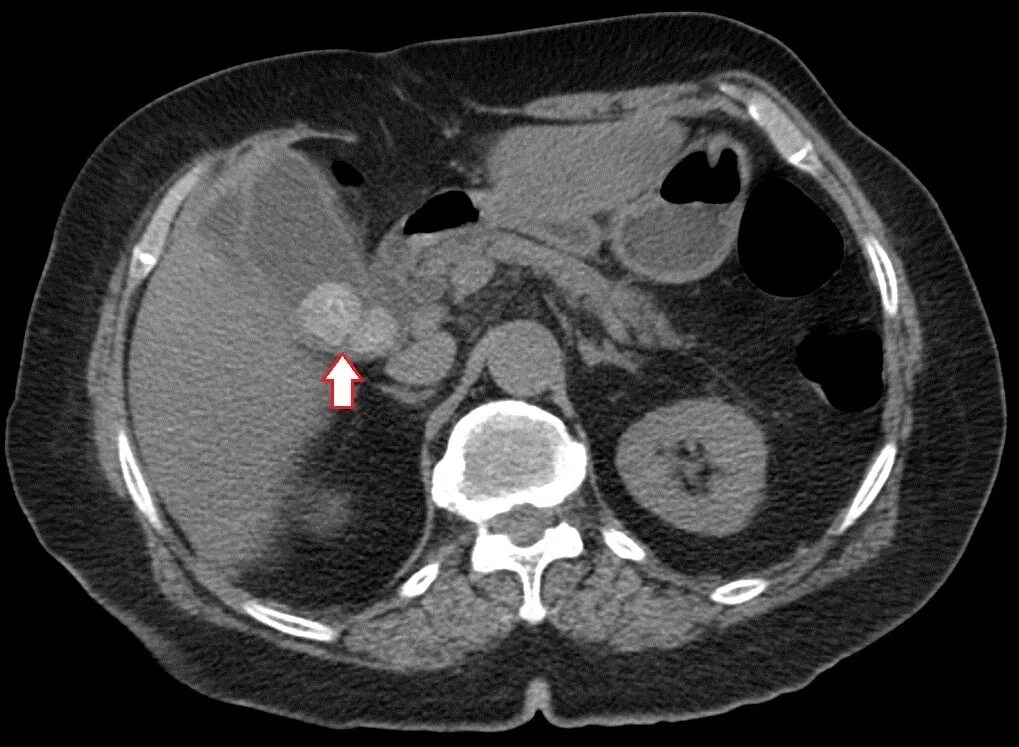

Камни в желчном мрт